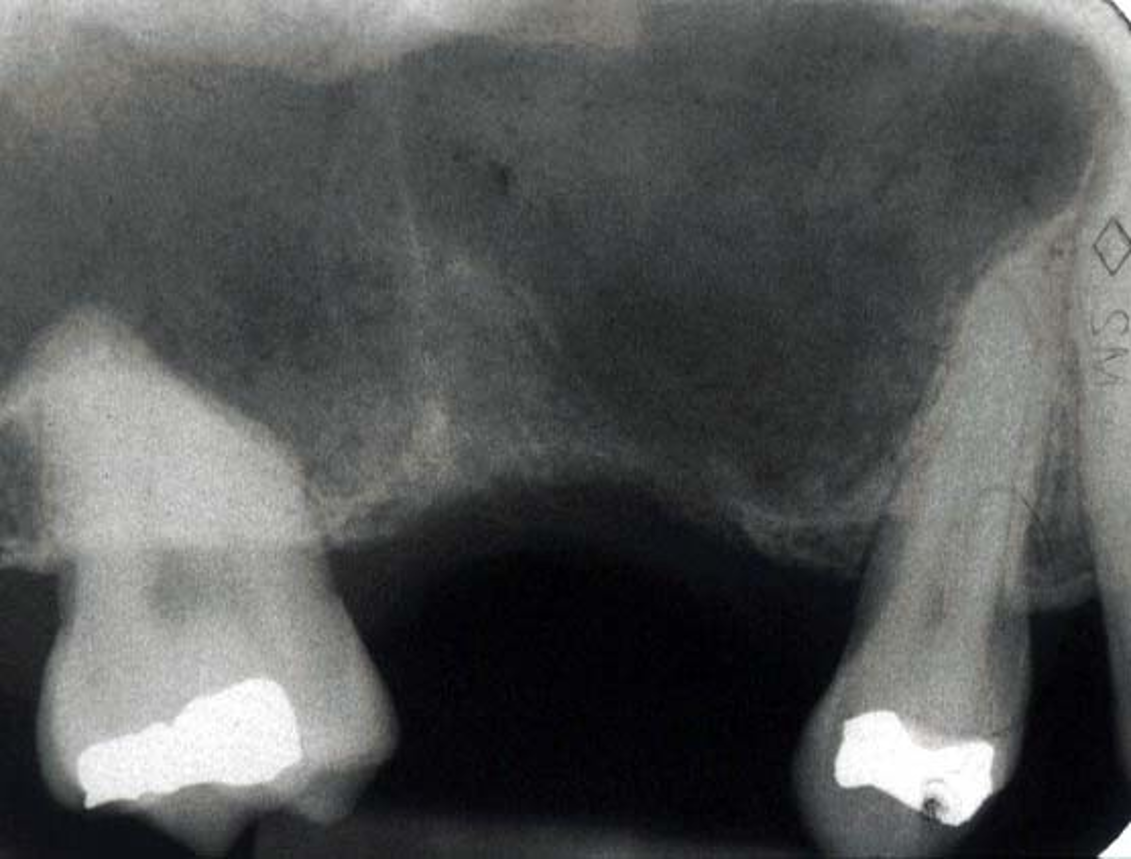

What is this radiograph highlighting?

• OAF

• Can see loss of bone and communication created